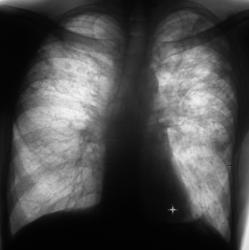

Впечатление о положительной динамике. Сохраняються плотные очаги.

А куда денешь 2 полости справа на уровне 2-3 ребер, и очаговые тени в верхних и средних полях с 2 сторон в фазе инфильтрации?

Насчёт полостей, на мой взгляд не убедительно; оценка плотности очагов, такие тонкие и принципиальные вопросы решаються не в интернете, а по снимкам с учётом R-архива, возможно с использованием дополнительных исследований( R-скопии и т.д.).  С увжением Морозов Александр.